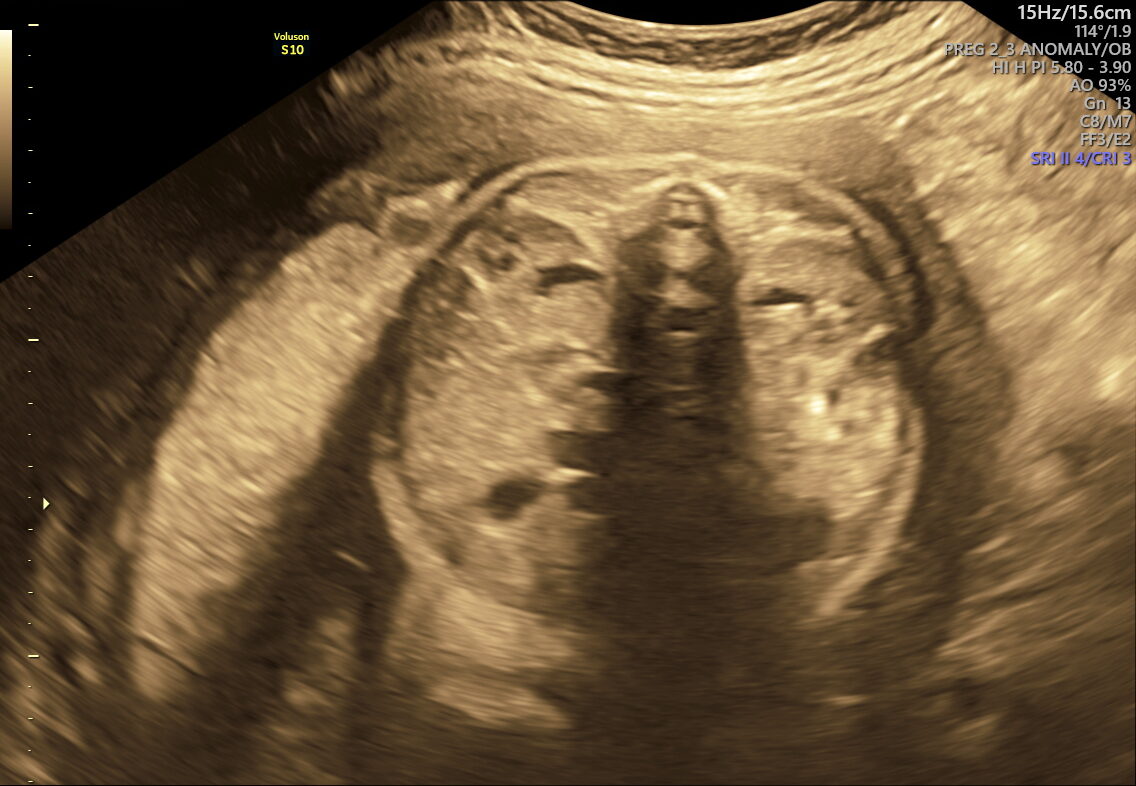

As your pregnancy journey enters its final weeks, NESA Institute of Fetal Medicine offers the Fetal Well-being Scan—a specialized ultrasound performed between 28 and 40 weeks. This essential check ensures your baby’s health and readiness for birth, giving you and your family confidence and clarity as you approach delivery.

This scan is designed to assess multiple aspects of your baby’s well-being and the mother’s preparedness for labour. Here’s what it covers:

- Vital Functions: Measures movements, breathing, and heart rate to make sure your baby is thriving.

This scan focuses on confirming birth readiness and spotting sudden issues that may arise close to your due date. It includes detailed Doppler studies to check blood flow in the umbilical cord and brain, ensuring your baby gets enough oxygen and nutrients.